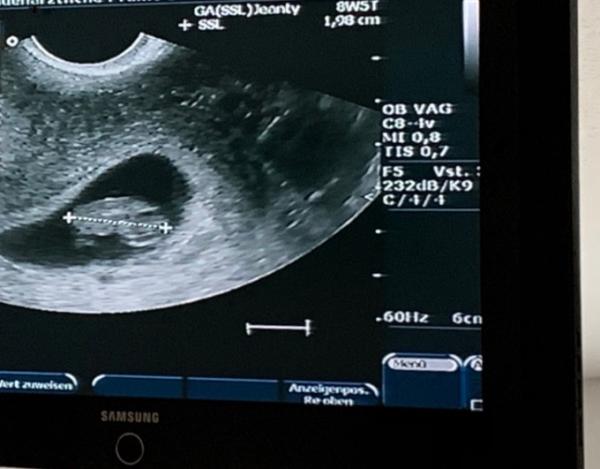

Das ganze Daumen drücken hat geholfen! Unserem kleinen Wunder geht es hervorragend und misst jetzt gut 2cm. Alles zeitgerecht. Wegen der Blutung, das konnte der Arzt sich auch nicht erklären. Habe gleich „die Spritze“ bekommen (da ich Rhesusfaktor negativ bin) mein normaler Gyn Termin ist heut um 13:30Uhr. War schon am überlegen ob ich den absage... die hört das sicherlich nicht gerne das ich bei meinem anderen Arzt war mal sehen. Bild hänge ich euch mal dran-weil ihr so fest an und geglaubt habt!

Bild zu Wieder zurück ! - Forum für April - Mamis